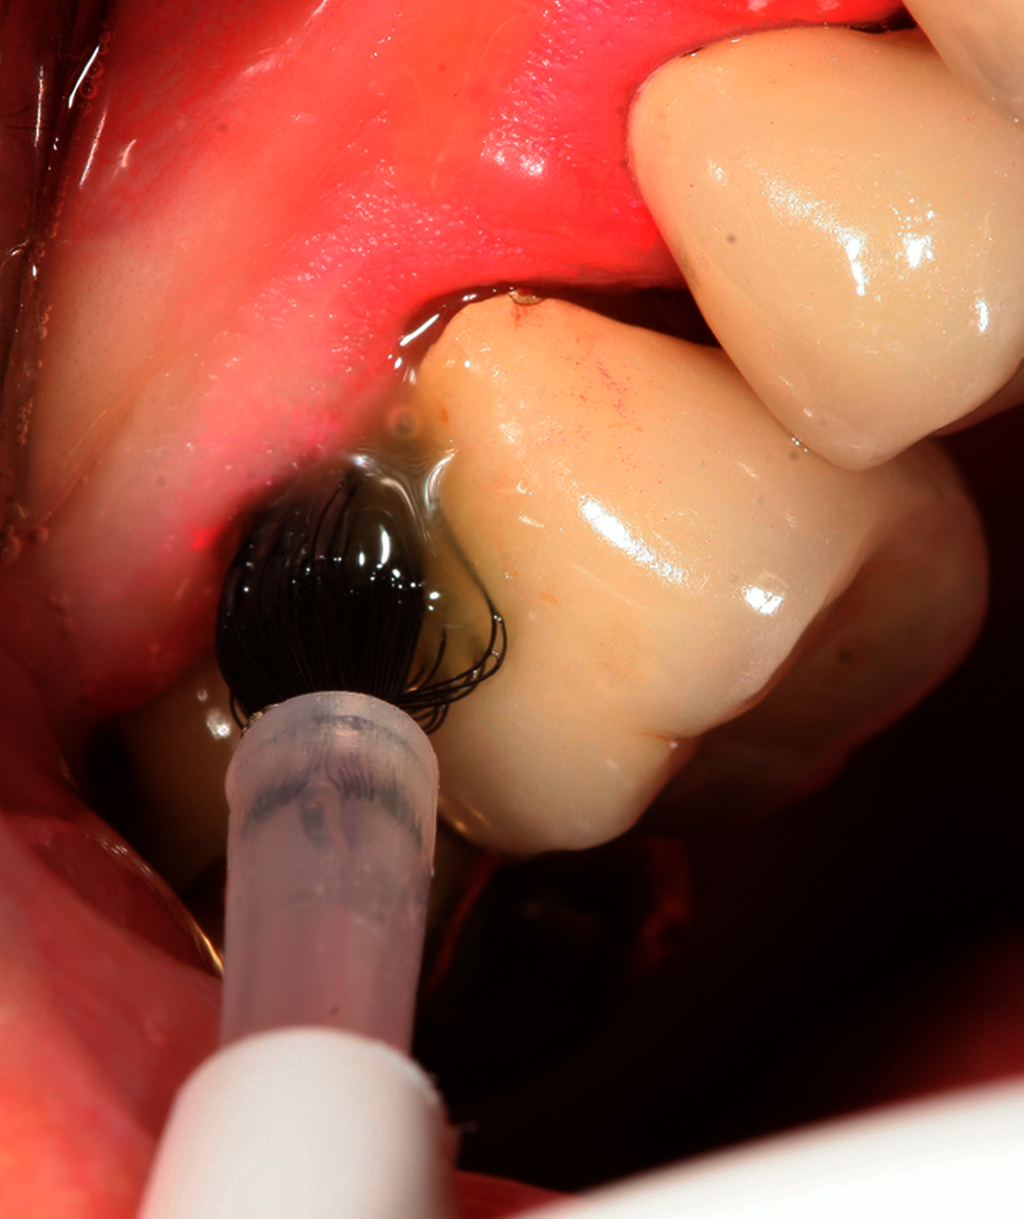

Eine vorhergehende spezifische systematische Analyse zur aPDT aus dem Jahr 2017 von elf klinischen Studien konnte zumindest kurzfristig (drei Monate) eine zusätzliche Taschenreduktion von 0,12 mm zur PMPR nachweisen [Xue et al., 2017]. Unberücksichtigt blieben in all diesen Untersuchungen aber relevante Betrachtungen zur Kosten-Nutzen- und Kosten-Effektivität-Relation. Auch ist der Zulassungsstatus der bei der aPDT verwendeten Farbstoffe/Photosensitizer in Deutschland für die subgingivale Applikation unklar und subantimikrobielles Doxycyclin (SDD) besitzt in Deutschland gar keine Zulassung, weshalb eine modifizierte Empfehlung 4.16 erfolgte.